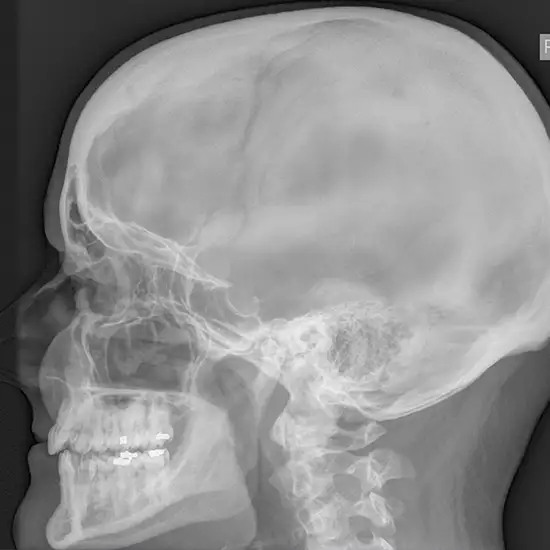

Mastoid refers to the temporal bone of the skull lying behind the ear. The mastoid bone is examined from the side during the oblique view X-ray test. Low radio waves are sent through the ear and lower part of the head, just like an X-ray. The waves look at the inside of the area and make an image on the computer screen.

The x-ray oblique view exam provides valuable mastoid information. It gives the following mastoid pathology results:

• Mastoid cellularity

• Cortical bone width

• Mastoid symmetry

• Mastoid cavity preservation detection

• Cholesteatoma information.